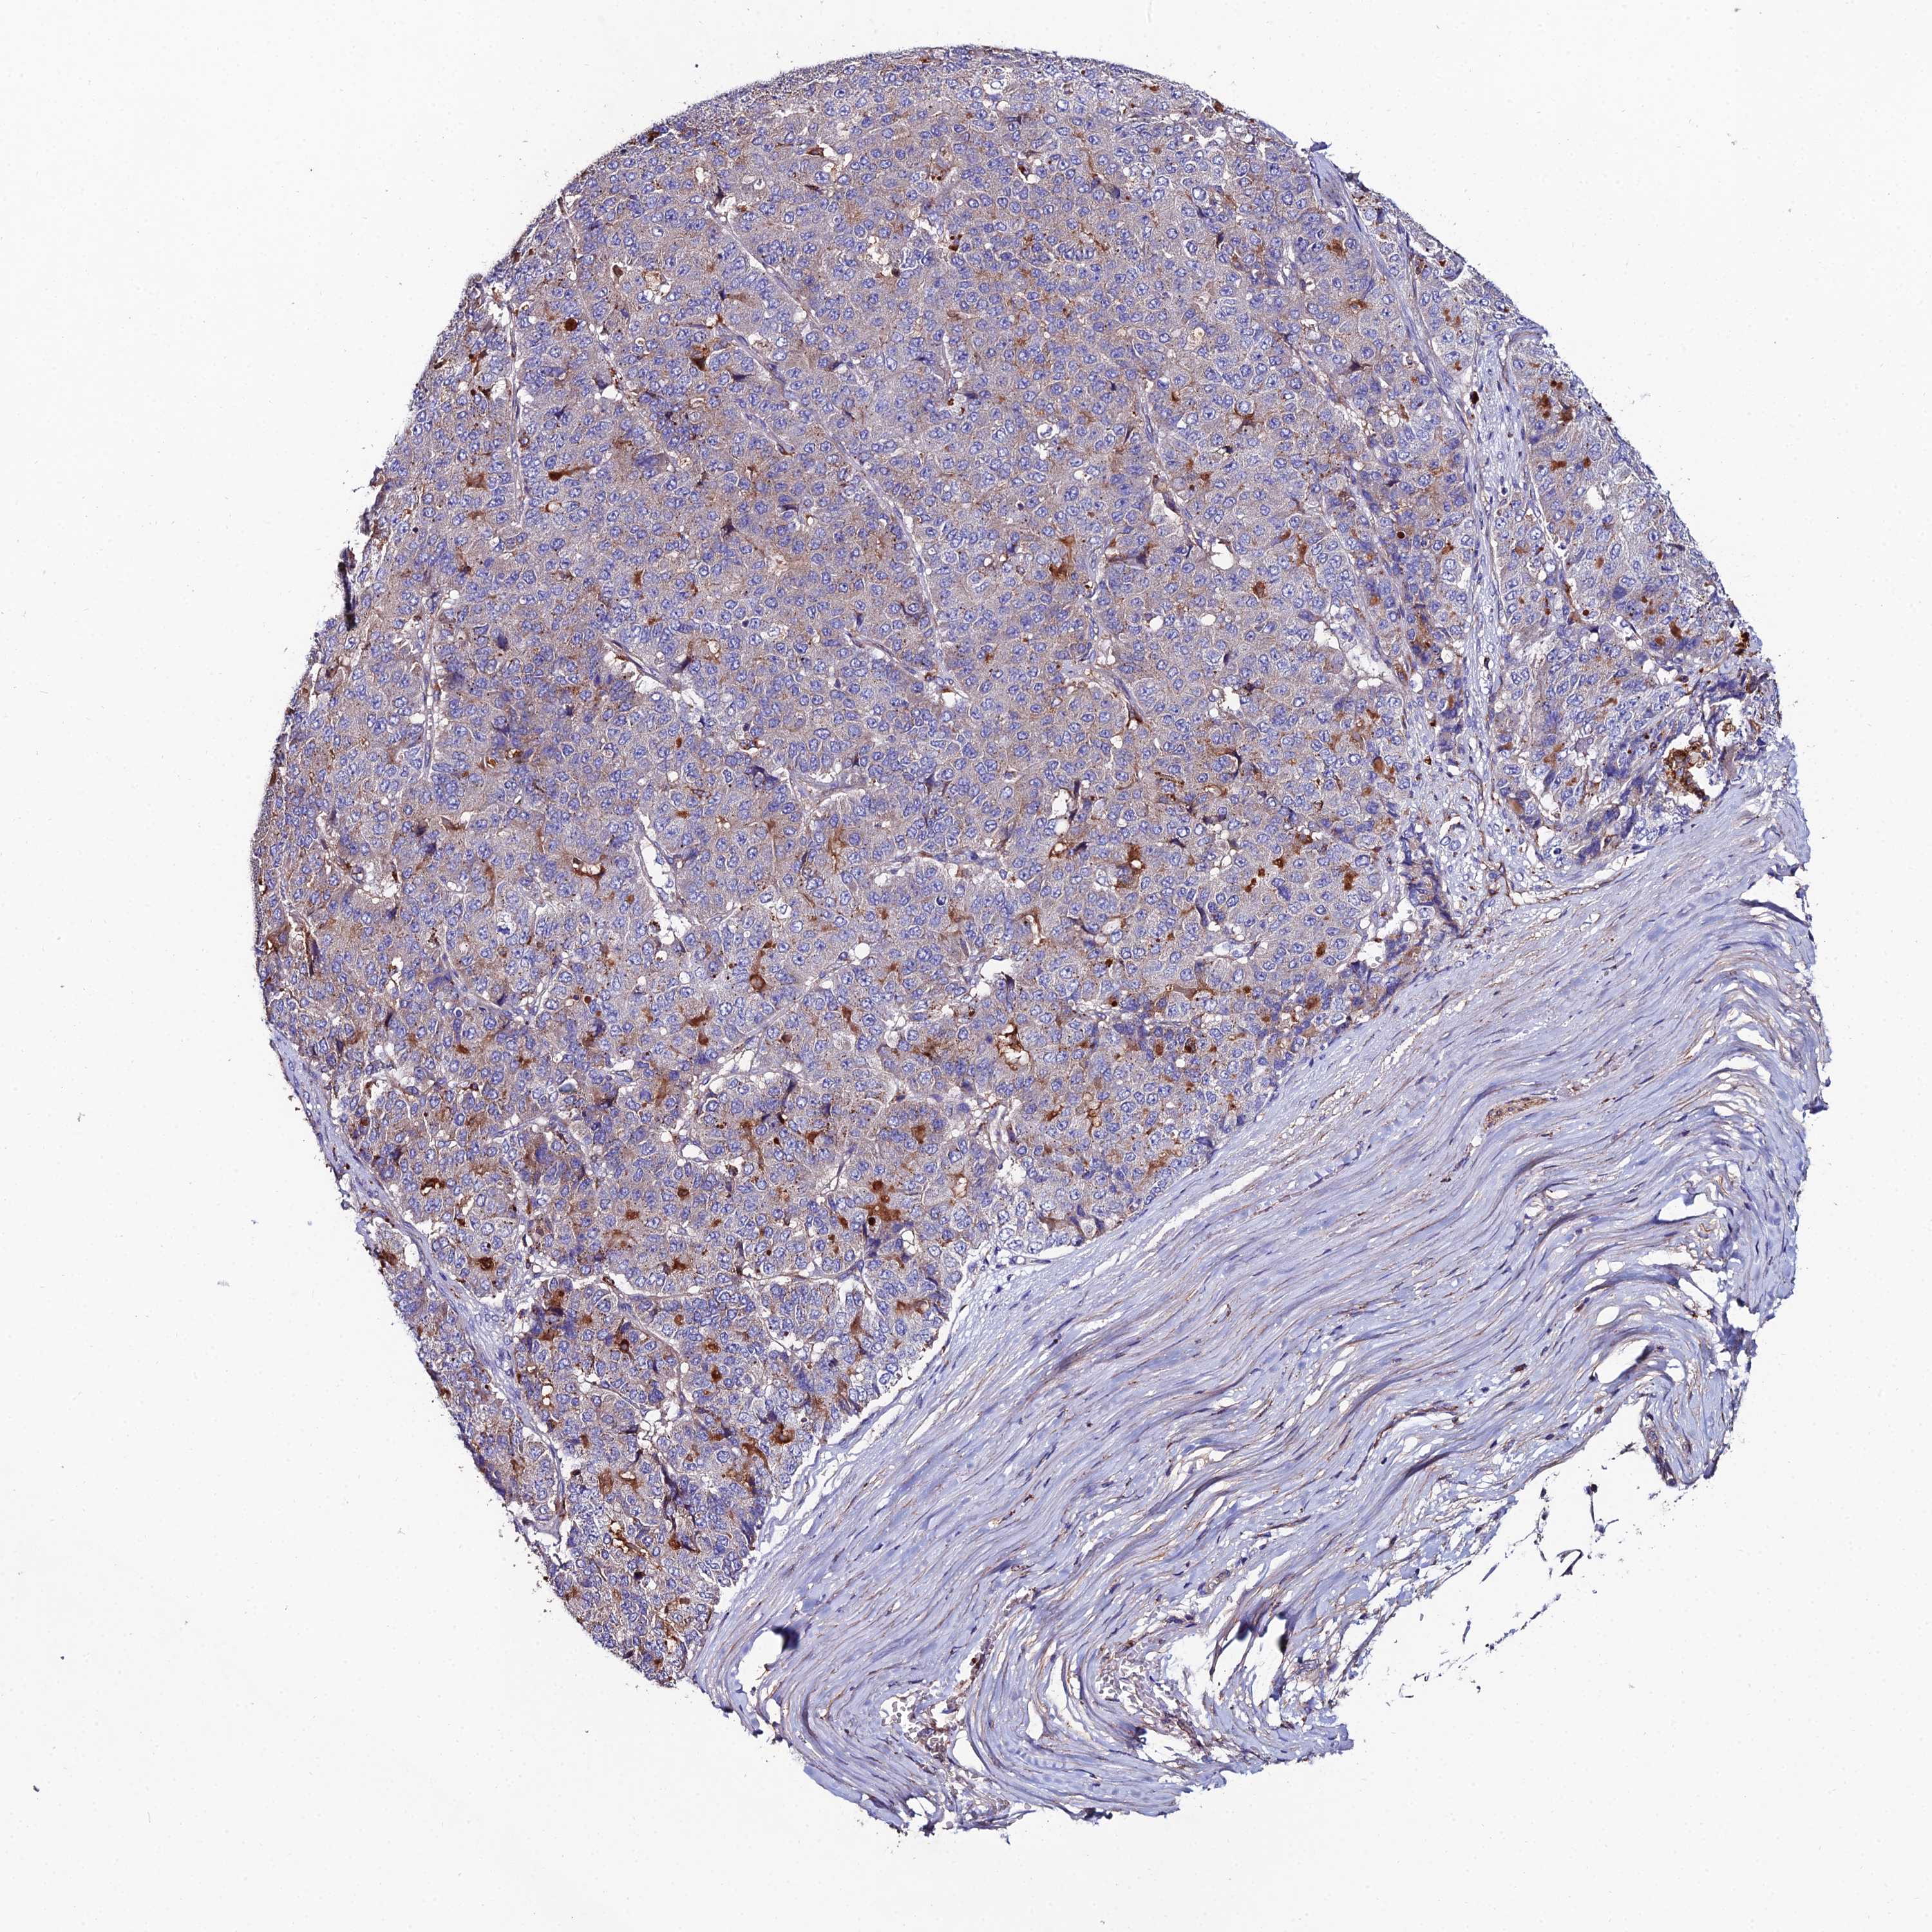

PANCREATIC CANCER - Protein expressioni

A mouse-over function shows sample information and annotation data. Click on an image to view it in a full screen mode. Samples can be filtered based on level of antibody staining by selecting one or several of the following categories: high, medium, low and not detected. The assay and annotation is described here.

Note that samples used for immunohistochemistry by the Human Protein Atlas do not correspond to samples in the TCGA dataset.

Antibody stainingi

Antibody staining in the annotated cell types in the current human tissue is reported as not detected, low, medium, or high, based on conventional immunohistochemistry profiling in selected tissues. This score is based on the combination of the staining intensity and fraction of stained cells.

Each image is clickable and will lead to virtual microscopy that enables deeper exploration of all samples and also displays staining intensity scores, fraction scores and subcellular localization as well as patient and tissue information for each sample.

Antibody HPA043823

Antibody CAB069427

Staining

High

Medium

Low

Not detected

Intensity

Strong

Moderate

Weak

Negative

Quantity

>75%

75%-25%

<25%

None

Location

Nuclear

Cytoplasmic/membranous

Cytoplasmic/membranous,nuclear

Adenocarcinoma, NOS